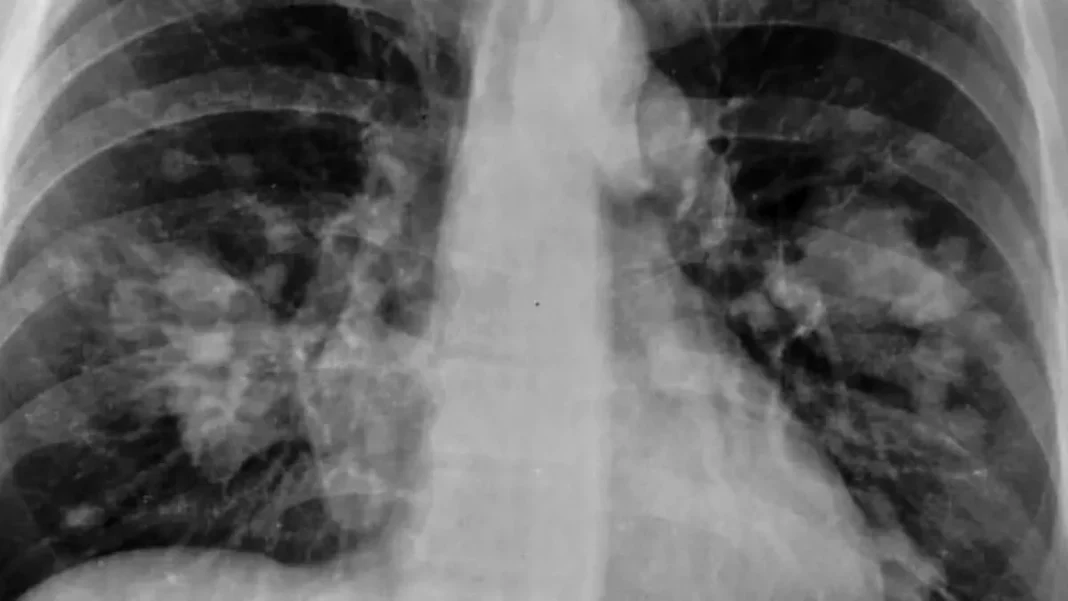

El cáncer de pulmón es una enfermedad extremadamente grave y devastadora y es una de las principales causas de muerte en todo el mundo. Este tipo de cáncer se desarrolla cuando las células anormales crecen de manera descontrolada en los pulmones. Por eso es tan peligroso, porque puede propagarse rápidamente a otros órganos, lo que dificulta su tratamiento y reduce las posibilidades de supervivencia. Sin embargo, acaban de descubrir una pastilla que logra reducir a la mitad el riesgo de morir por esta enfermedad. Te contamos más a lo largo de este artículo, así que sigue leyendo si te quieres enterar de todo.

Se están realizando numerosas investigaciones para mitigar los efectos del cáncer de pulmón. Se exploran diferentes enfoques terapéuticos, como la radioterapia, la quimioterapia y la terapia dirigida, con el objetivo de reducir los tumores, controlar los síntomas y mejorar la calidad de vida de los pacientes. Además, se investiga en tratamientos personalizados y nuevas terapias prometedoras, como la pastilla de al que te hablamos a continuación.